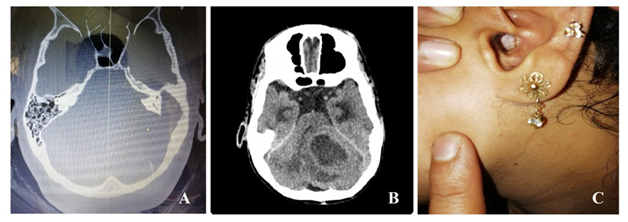

Regular follow up to 1year was done and showed improvement in hearing on repeating the audiometry and the graft has taken up well (Figure 1).

Figure 1 1A Shows erosion of the bone due to cholesteatoma. 1B shows cerebellar abscess and 1C Shows graft uptake after 1year follow-up.